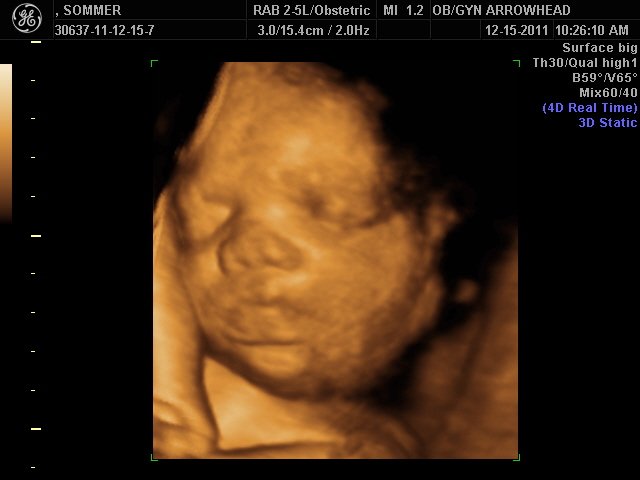

We offer complimentary 3D/4D Ultrasounds to all our OB patients around 30 weeks! The following photos are some examples of our work, shown with permission from our patients.